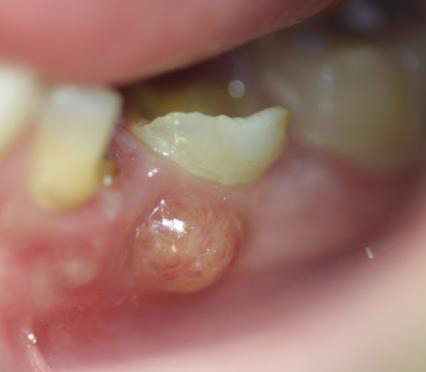

Absceso gingival / Gingival abscess

Descripción: Clinical examination revealed 7-mm probing depths, circumferentially around a mandibular implant, bleeding on probing, and the presence of exudate and gingival inflammatory edema

Se produce un aumento muy definido del volumen de la encía, generalmente en relación con un absceso periapical (extremo de la raíz de un diente) la zona se torna enrojecida e incluso puede rezumar exudado purulento.

A localized, purulent infection that involves the marginal gingiva or the interdental papilla.